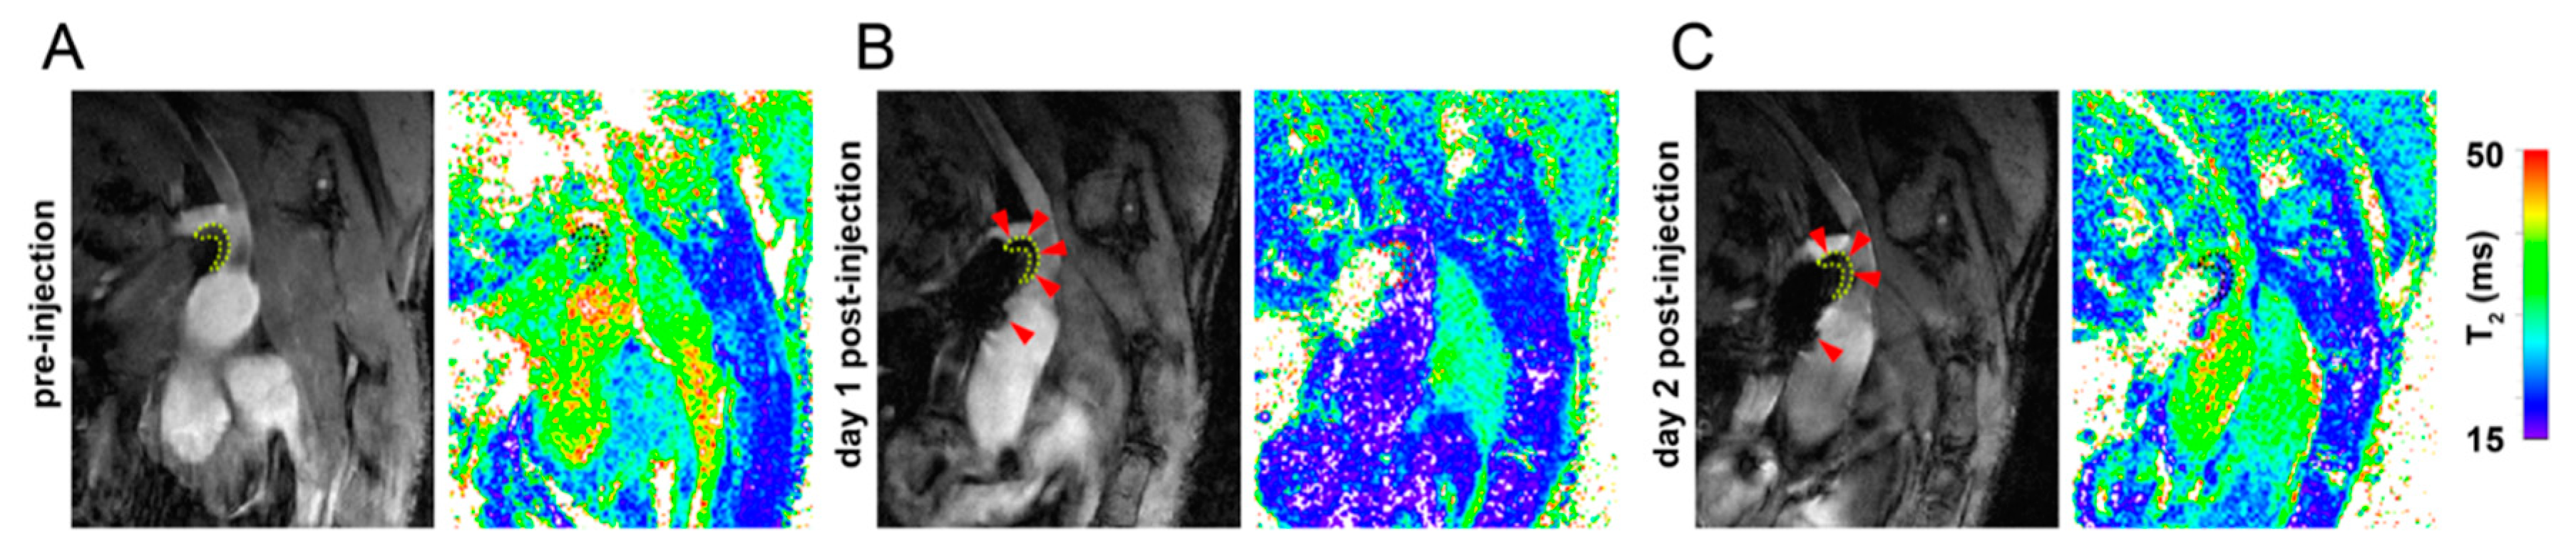

Iron Oxide Nanoparticle Uptake in Mouse Brachiocephalic Artery Atherosclerotic Plaque Quantified by T2-Mapping MRI

Moonen, R.P.M.; Coolen, B.F.; Sluimer, J.C.; Daemen, M.J.A.P.; Strijkers, G.J. Iron Oxide Nanoparticle Uptake in Mouse Brachiocephalic Artery Atherosclerotic Plaque Quantified by T2-Mapping MRI. Pharmaceutics 2021, 13, 279. https://doi.org/10.3390/pharmaceutics13020279